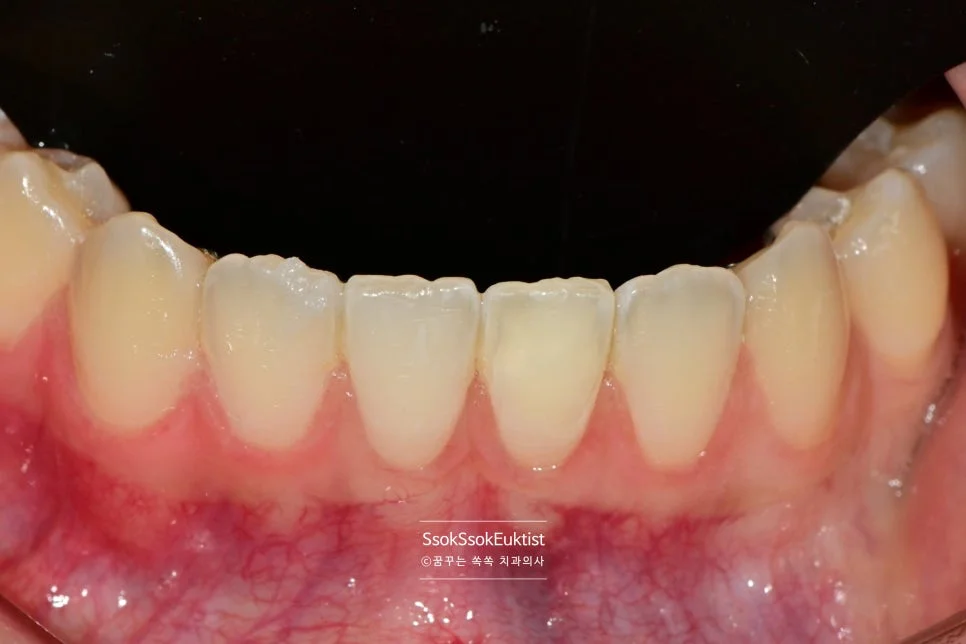

변색된 아래 앞니 클로즈업 — 주변 치아와 확연히 다른 색상

이 치아 색이 변한지는 1년 정도 되었고, 최근 갑자기 시려서 여러 군데 치과에 다녔는데 다 괜찮다는 말만 들었다고 합니다.

우리 치과에서는 신경치료 및 실활치 미백을 진단하고, 수면 마취를 통해 치료를 진행하기로 합니다.